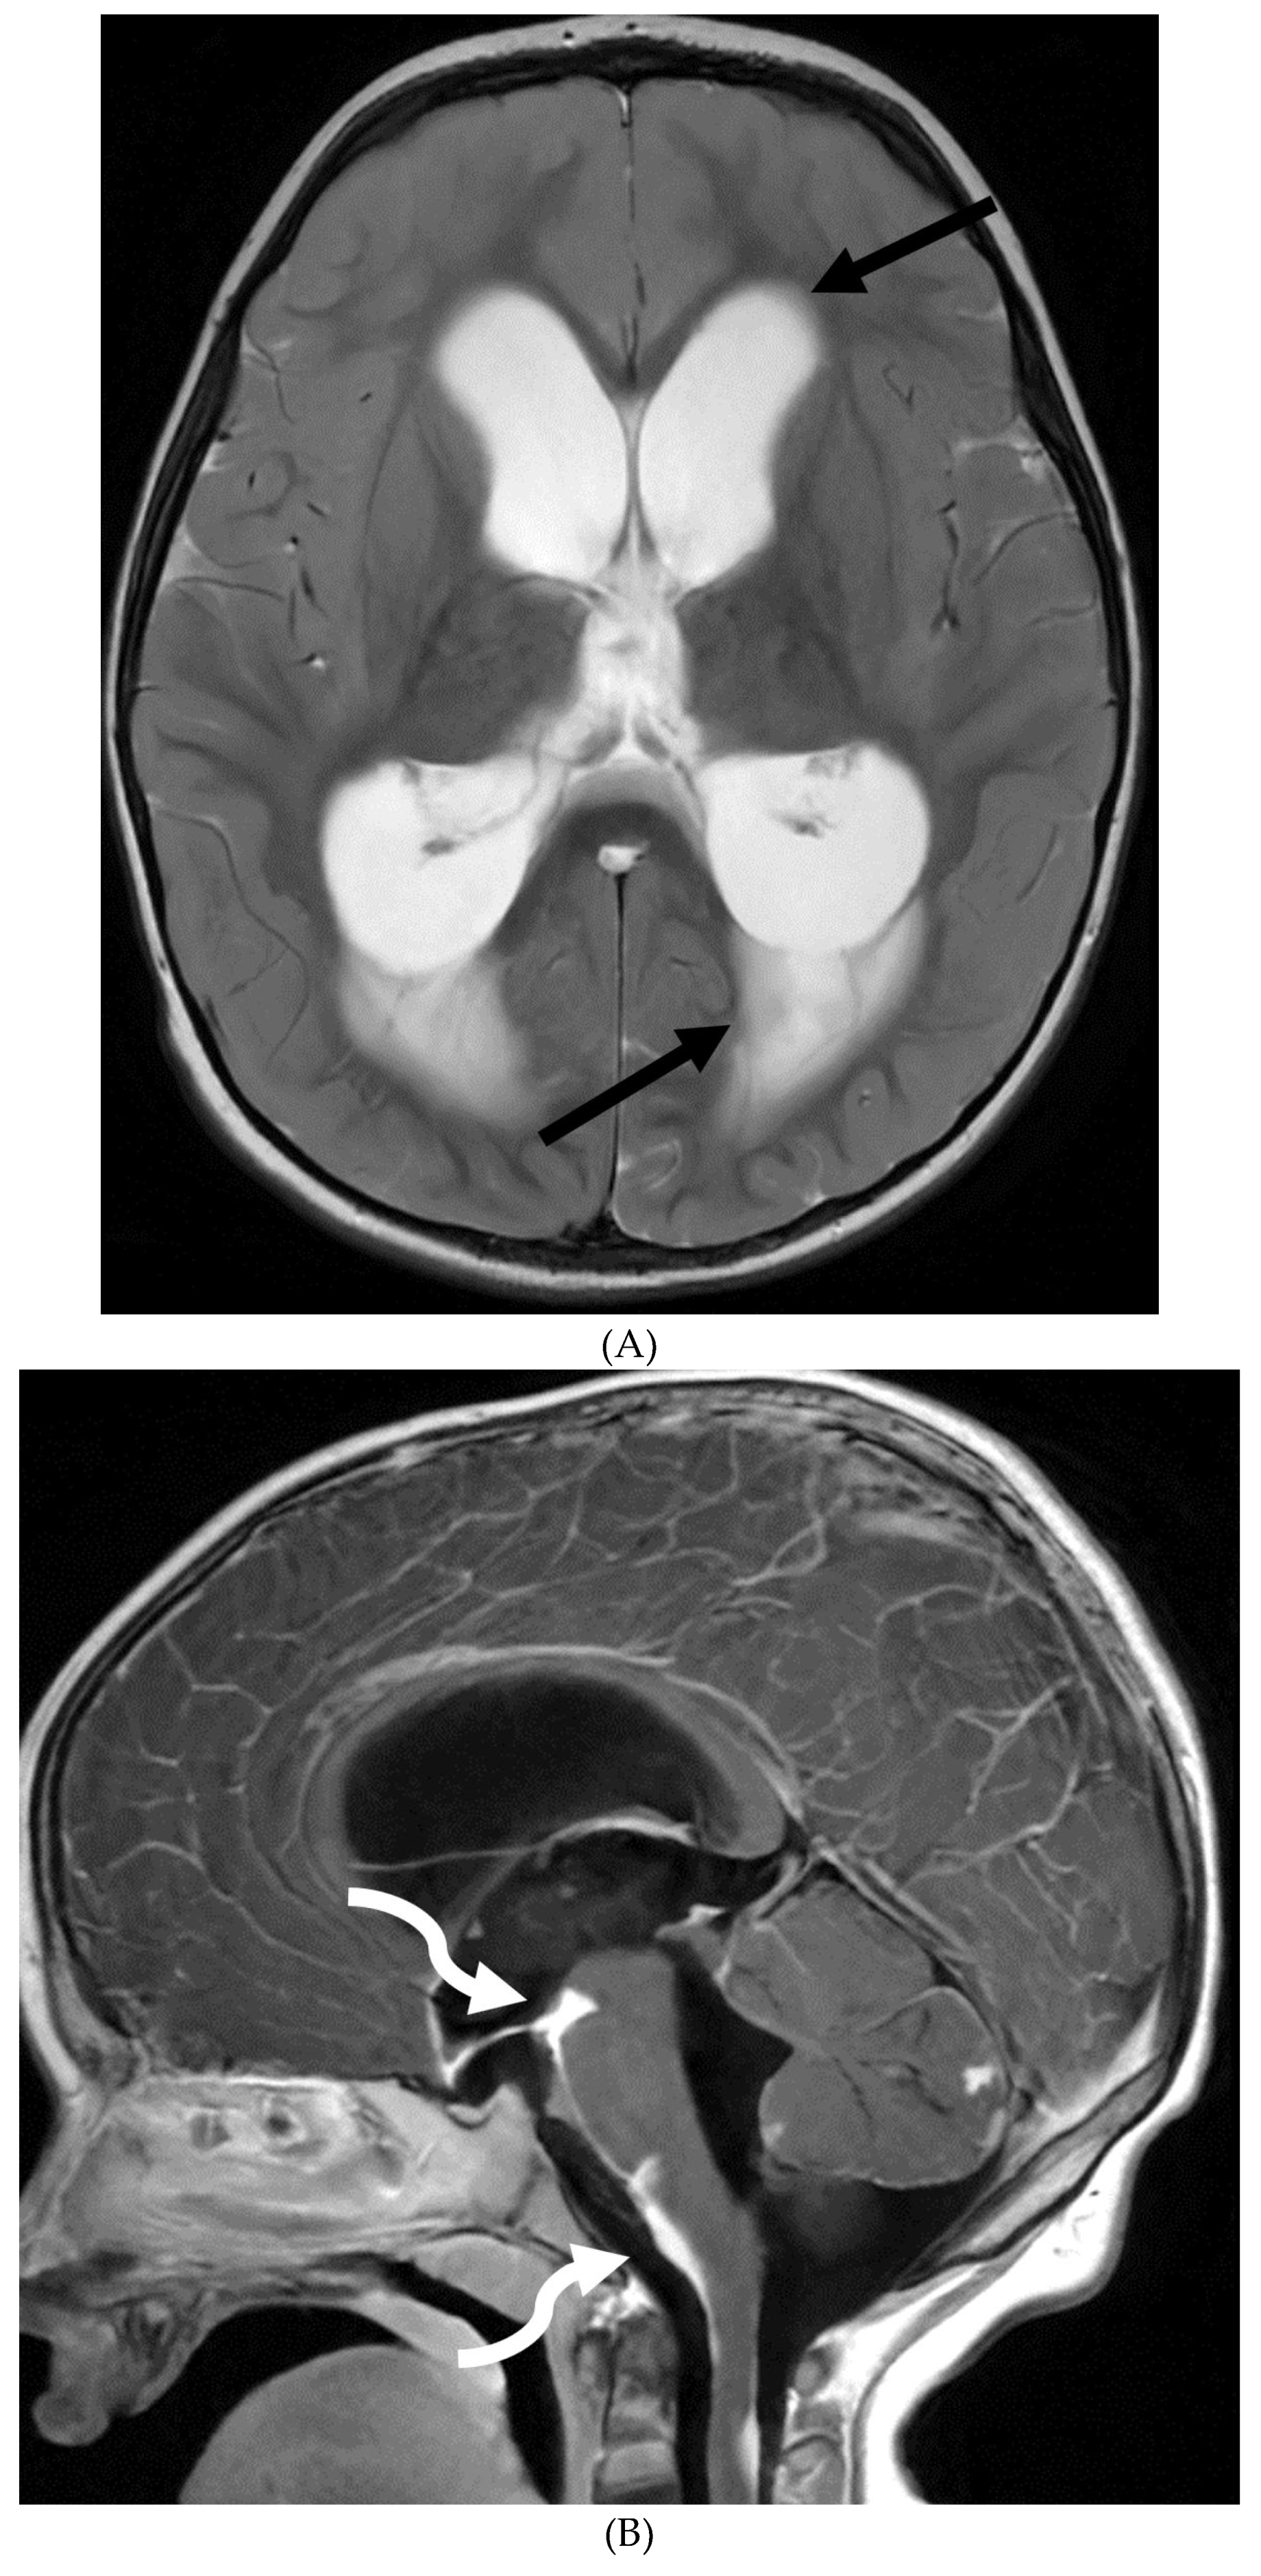

GUILLAIN BARRE SYNDROME

- Alkan O, Yildirim T, Tokmak N, Tan M. Spinal MRI findings of guillain-barré syndrome. J Radiol Case Rep. 2009;3(3):25-8. Epub 2009 Mar 1. PMID: 22470650; PMCID: PMC3303301. [CrossRef]

- Zuccoli G, Panigrahy A, Bailey A, Fitz C. Redefining the Guillain-Barré spectrum in children: neuroimaging findings of cranial nerve involvement. AJNR Am J Neuroradiol. 2011 Apr;32(4):639-42. Epub 2011 Feb 3. PMID: 21292802; PMCID: PMC7965877. [CrossRef]

- Fulbright RK, Erdum E, Sze G, Byrne T. Cranial nerve enhancement in the Guillain-Barré syndrome. AJNR Am J Neuroradiol. 1995 Apr;16(4 Suppl):923-5. PMID: 7611075; PMCID: PMC8332311.

- Yikilmaz A, Doganay S, Gumus H, Per H, Kumandas S, Coskun A. Magnetic resonance imaging of childhood Guillain-Barre syndrome. Childs Nerv Syst. 2010 Aug;26(8):1103-8. Epub 2010 Jun 17. PMID: 20556395. [CrossRef]

- Byun WM, Park WK, Park BH, Ahn SH, Hwang MS, Chang JC. Guillain-Barré syndrome: MR imaging findings of the spine in eight patients. Radiology. 1998 Jul;208(1):137-41. PMID: 9646804. [CrossRef]

- Malhotra A, Zhang M, Wu X, Jindal S, Durand D, Makhani N. MRI findings of optic pathway involvement in Miller Fisher syndrome in 3 pediatric patients and a review of the literature. J Clin Neurosci. 2017 May;39:63-67. Epub 2017 Feb 10. PMID: 28209311. [CrossRef]

- Gallardo E, Sedano MJ, Orizaola P, Sánchez-Juan P, González-Suárez A, García A, Terán-Villagrá N, Ruiz-Soto M, Álvaro RL, Berciano MT, Lafarga M, Berciano J. Spinal nerve involvement in early Guillain-Barré syndrome: a clinico-electrophysiological, ultrasonographic and pathological study. Clin Neurophysiol. 2015 Apr;126(4):810-9. Epub 2014 Aug 21. PMID: 25213352. [CrossRef]